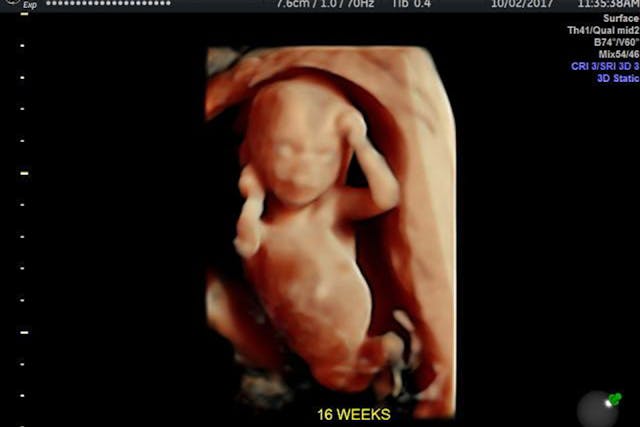

One day after he went on TV to claim he was worried sick about his family’s disappearance, Chris Watts was arrested for their murders. The body of Chris’s wife, Shannan, was recovered on the property of Anadarko, the company where he works. Shannan was reportedly 15 weeks pregnant with the couple’s third child – a son who was to be named Niko.

Since Shannan and her preborn son Niko were in Colorado at the time of their murder, Chris has not been charged with a fourth murder — that of his son. Instead, he faces three counts of first degree murder and a handful of lesser charges. The charges have not been formally finalized, however; and prosecutors could add charges by Monday.

Sadly, even if Chris Watts is convicted of a triple murder, one little boy’s life will not be counted under the law. It will be as if Niko Watts, the loved son of Shannan Watts and brother to Bella and Celeste, never even existed.